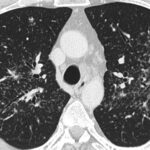

La intoxicación por bloqueadores beta-adrenérgicos es un fenómeno clínico complejo que se asocia a la administración excesiva o inadecuada de fármacos que actúan sobre los receptores beta-adrenérgicos del sistema nervioso…